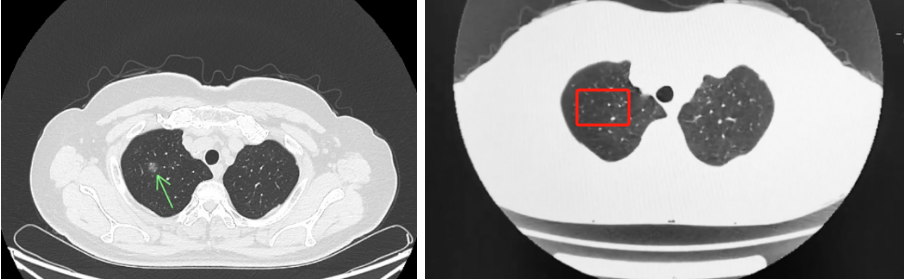

深夜咳血,DeepSeek指引希望:湖北省第三人民医院呼吸介入团队成功救治56岁大咯血患者